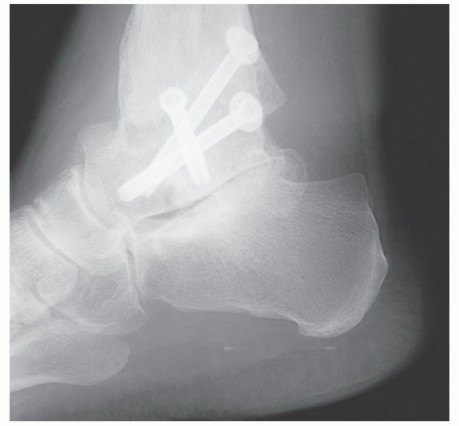

DEFINITION An isolated subtalar arthrodesis can be used in the treatment of a myriad of different hindfoot co…